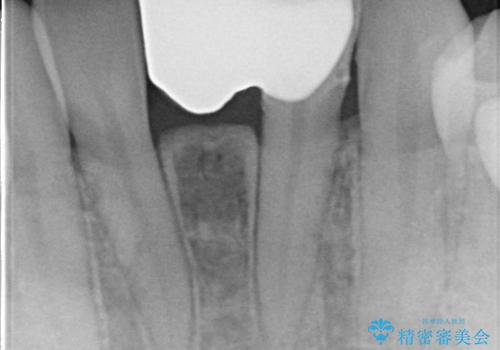

- 昔入れたメタルインレーの下にむし歯が再発したため治療を行った患者様です。

メタルインレーは汚れが付着しやすく、適合も悪いことがあるため、むし歯が再発しやすかったと思われます。

フロスなどの日常の清掃はもちろん不可欠ですが、メタルインレーより汚れが付着しずらいセラミックインレーにて今回は治療を行いました。